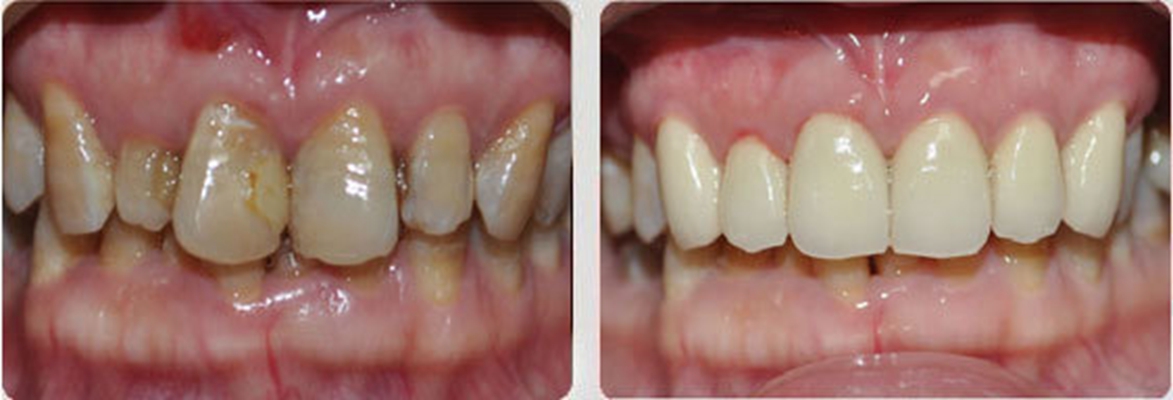

牙周炎圖片

牙周袋 (7)